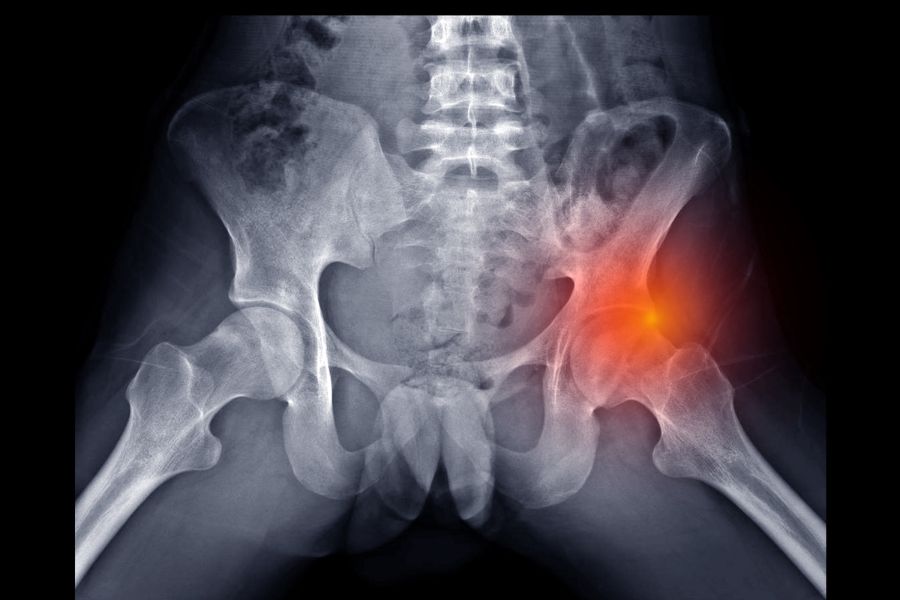

Kalça eklemi, vücudun en hareketli ve en fazla yük taşıyan bölgelerinden biridir. Ancak bazı bireylerde bu eklemdeki yapısal uyumsuzluklar nedeniyle hareket sırasında kemikler birbiriyle sürtünür ve zamanla ağrıya neden olur. Bu duruma “kalça sıkışması sendromu” (Femoroasetabular impingement - FAI) adı verilir. Özellikle genç ve aktif bireylerde görülen bu durum, erken teşhis edilmediğinde ilerleyen dönemlerde kireçlenmeye ve hareket kısıtlılığına yol açabilir. Peki kalça sıkışması nedir, neden olur ve nasıl tedavi edilir? İşte detaylı rehberimiz…

Kalça sıkışması, uyluk kemiğinin başı (femur başı) ile kalça yuvası (asetabulum) arasında normal dışı temas olması sonucu oluşan bir ortopedik sorundur. Bu sıkışma, eklem hareketi sırasında iki kemik yüzeyinin birbirine sürtmesiyle kıkırdak ve labrum (eklem dudağı) dokusunda hasara neden olur. Zamanla bu sürtünme ağrıya, hareket kısıtlılığına ve erken yaşta kalça artrozu (kireçlenme) gelişimine yol açabilir.

• Kasık bölgesinde ya da kalça önünde batıcı, sıkışma tarzı ağrı